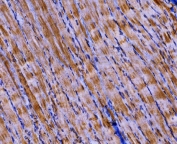

IHC staining of FFPE mouse skeletal muscle tissue with PKM2 antibody. HIER: boil tissue sections in pH8 EDTA for 20 min and allow to cool before testing.